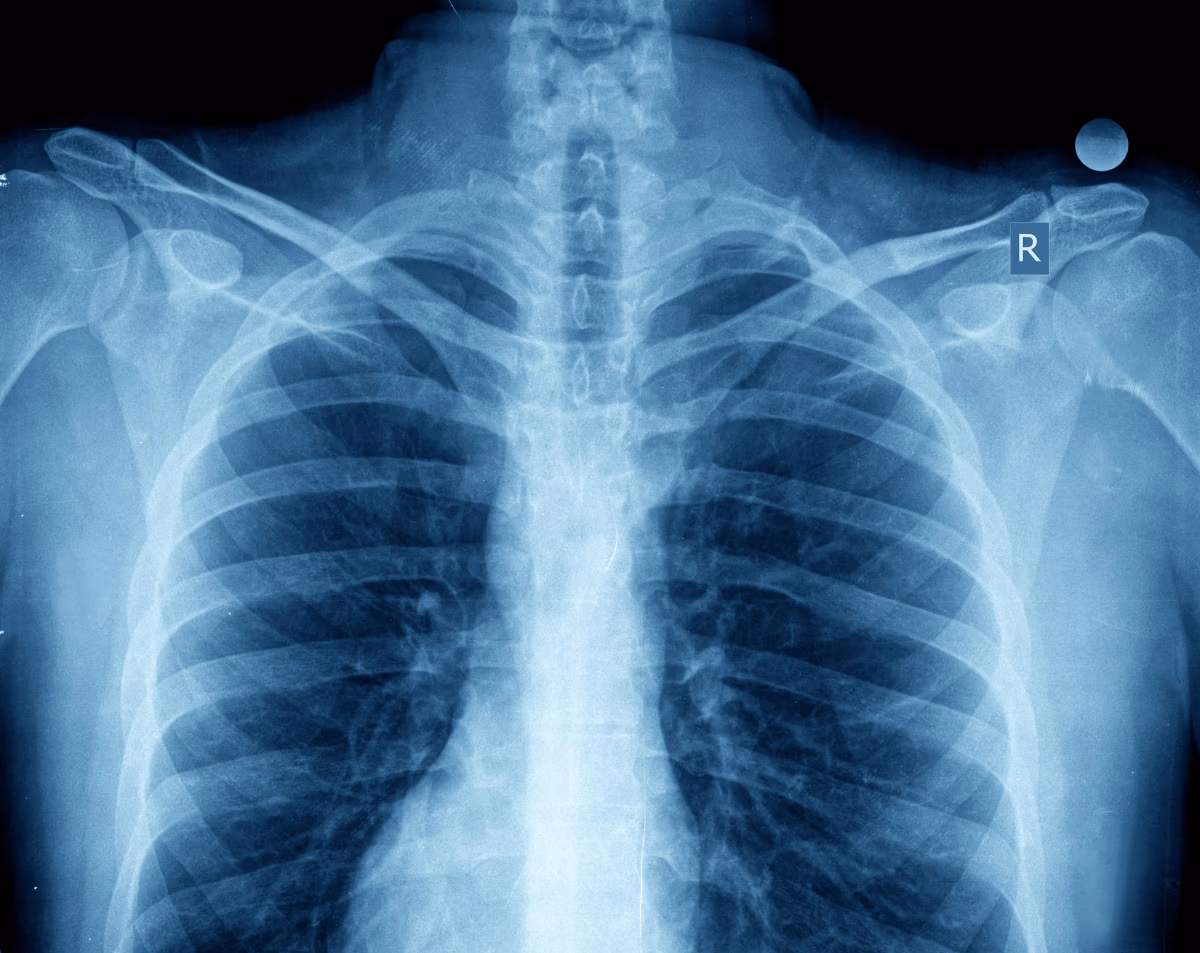

A chest X-ray is one of the most common and important diagnostic tools in medicine. It produces clear images of your heart, lungs, airways, blood vessels, and chest bones. Physicians rely on it to diagnose respiratory conditions, detect infections, and monitor heart and lung health. At Desert Mobile Medical, we make this process even more convenient by delivering hospital-grade digital chest X-rays directly to you—at home, at work, or in a care facility.